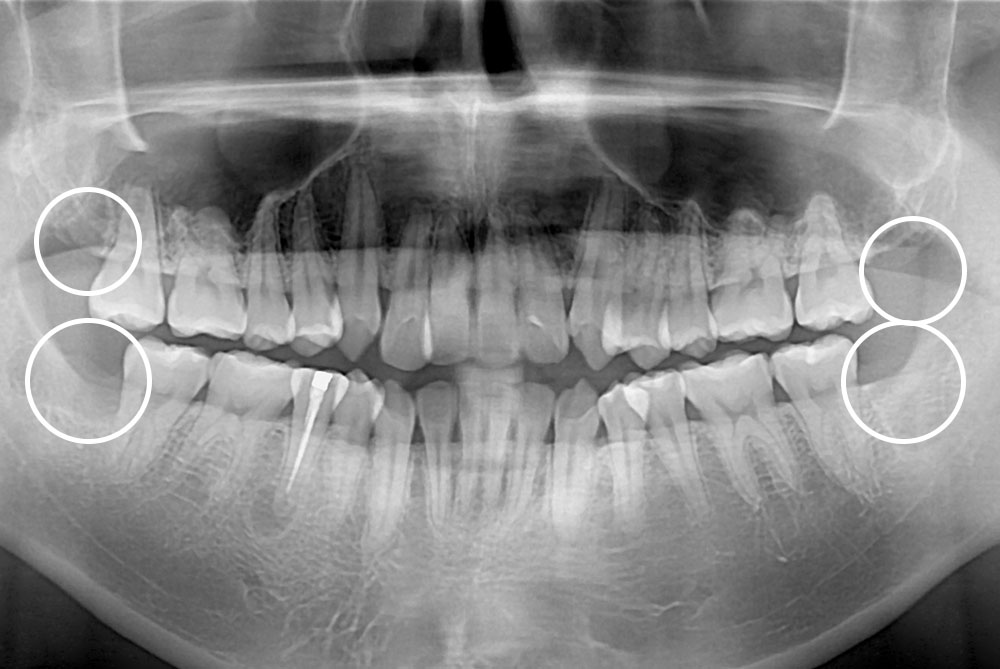

[사랑니] 매복 사랑니 발치

치료전 : 2015-03-13